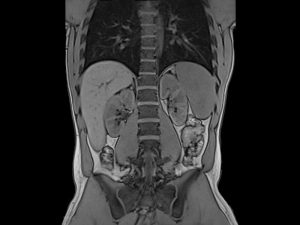

سی تی اسکن اسپیرال شکم و لگن

روش خواندن عکس ام ار ای از دیسک کمر

بهترین زمان سونوگرافی شکم و لگن